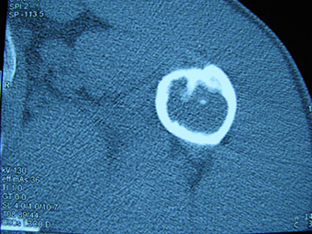

标题: X6404B:肱骨骨质破坏(CT片) [打印本页]

标题: X6404B:肱骨骨质破坏(CT片)

男,50岁,左肩部轻微疼痛,活动不便5个月就诊,近十天加重,无红肿热,间断理疗治疗无好转,既往5个月前左肩轻微拉伤史

骨巨?动脉瘤样骨囊肿?

内生软骨瘤。

内生软骨瘤。

内生软骨瘤?-----------

年纪大了,先要排除转移瘤。

髓腔内软组织肿块并斑片状钙化,考虑高分化软骨肉瘤可能性大。

考虑骨巨或动脉瘤样骨囊肿。

内生软骨瘤可能性大,期待结果。

孤立性骨囊肿。

内生软骨瘤可能性大

其内可见钙化,考虑软骨源性肿瘤,内生软骨瘤可能

但由于年龄较大,恶性软骨肉瘤待排

肱骨头内巨大软组织肿块并斑片状钙化,内生软骨瘤?骨巨细胞瘤?软骨粘液样纤维瘤?期待结果!

髓腔内软组织肿块并斑片状钙化,考虑高分化软骨肉瘤可能性大。

内生软骨瘤可能性大

肱骨头内巨大软组织肿块并斑片状钙化,内生软骨瘤?骨巨细胞瘤?软骨粘液样纤维瘤?期待结果

考虑内生软骨瘤?骨巨细胞瘤?

内生软骨瘤?骨巨细胞瘤?

先要排除转移瘤。